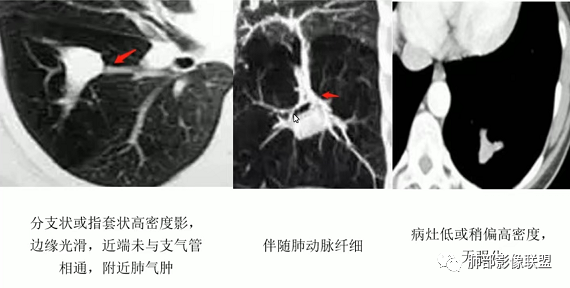

一、支气管闭锁

1、支气管粘液栓的表现∶多位于肺门的外侧,紧邻肺门,少数位于肺野外周,走行与正常支气管走行类似,而原来相对应区域的支气管缺失或阻塞。呈分支状或指套状结构,近端闭锁,不与支气管相通,与CT扫描层面平行时为"V"形、"Y"形或多个分支条状,与CT层面垂直时为类圆形结节状,MSCT应用MPR可行任意角度重组观察黏液栓的形态及其与近端支气管、血管的关系。黏液栓多为水样密度或软组织密度(较粘稠的黏液).但增强扫描无强化;内可有气体影,形成液气平面。伴随肺动脉细小。

2、间接征象∶周围肺气肿或阻塞性炎性改变。绝大部分都伴随不同程度的肺气肿,常见的是较大面积的肺气肿,其内血管比较纤细,也有报道可以不伴随肺气肿,但是罕见。

柱状支气管扩张-轨道征(柱状支扩)。增厚的支气管壁与扩张中空的支气管类似于轨道,边缘比较光滑肺部像聪驱远端稍增宽或等宽,走形较自然、顺畅。增厚的支气管壁类似于铁轨,见于柱状扩张。腔内有粘液栓时要与血管鉴别。

静脉曲张样扩张∶ 主要是支气管壁破坏更明显,边缘凹凸不平,各段扩张的程度不一,支气管呈曲张的静脉一样或串珠状。是柱状扩张向囊状扩张过渡的一个阶段,是牵拉性支气管扩张常常会表现的一种形式。

支气管扩张--粘液栓。

支气管扩张--树芽征。树芽征∶指CT表现为靠近胸膜下区小叶中心直径为3~5 mm的分支部影像联附状线影和与其相连的细支气管横断面结节影,状如春天里树上挂满树芽,即树芽征。是细支气管扩张、阻塞的特征影像之一。树芽征不是一个病,而是一组疾病可能出现的CT征象,胸部X线片不能发现如此细小的病变。